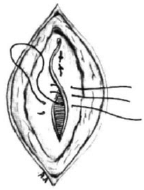

Nas suturas interrompidas os fios são fixados separadamente, podendo variar a tensão de acordo com a necessidade em cada ponto. É considerada mais segura, já que o rompimento de um ponto não inviabiliza a sutura toda. É menos isquemiante, confere maior permeabilidade à ferida e consegue força tensil maior e de modo mais rápido. Como desvantagens, possui uma elaboração mais lenta e trabalhosa. Relacione os tipos de sutura com as imagens e assinale a alternativa que apresenta a ordem correta.

1. Sutura em Jaquetão.

2. Sutura em “X” ou Sultan.

3. Sutura de Mayo.

4. Sutura de Halsted.